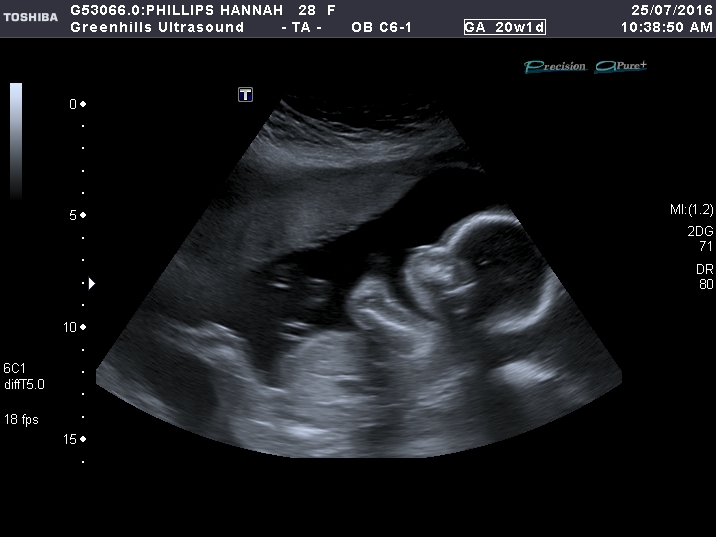

Middle is 20 weeks